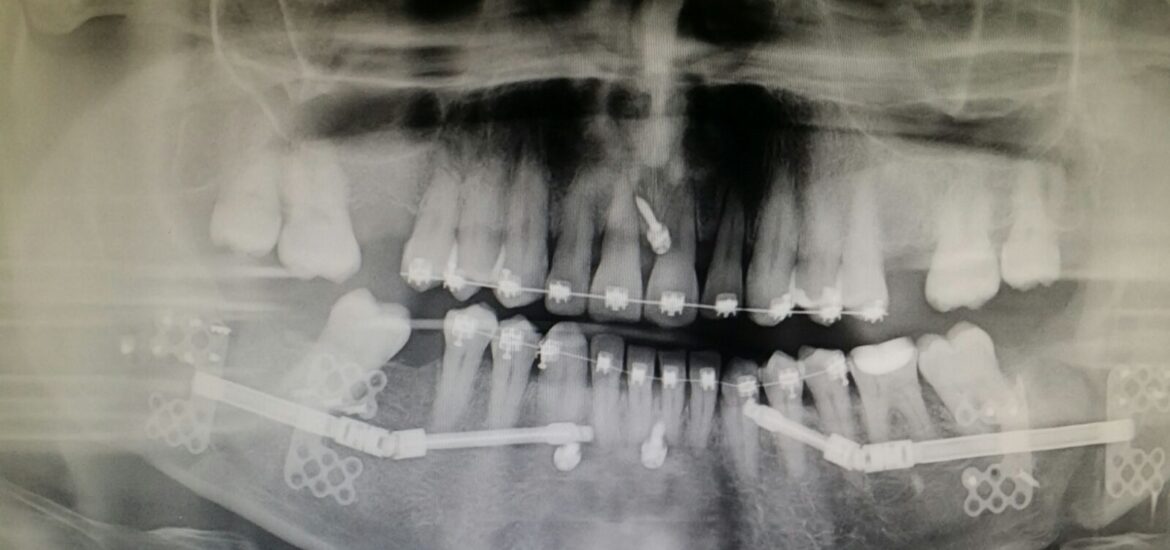

- Diagnóstico de Precisión: No adivinamos. Usamos tecnología de imagen avanzada para ver exactamente dónde está tu disco y en qué estado se encuentra el hueso.